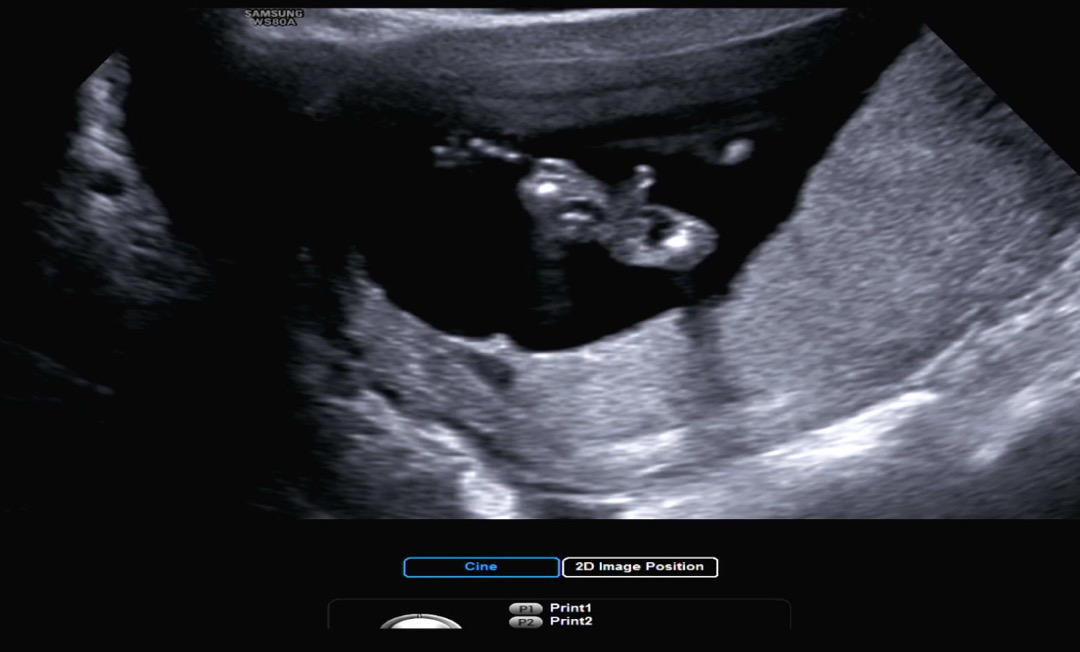

15주성별

의사쌤이 이사진보면서 자긴알거같다하는데 성별이 뭘꺼ㅏ요 ㅠㅠ

ㅋㅋㅋㅋㅋㅋ엉덩이 가운데 뿅 아들같아요